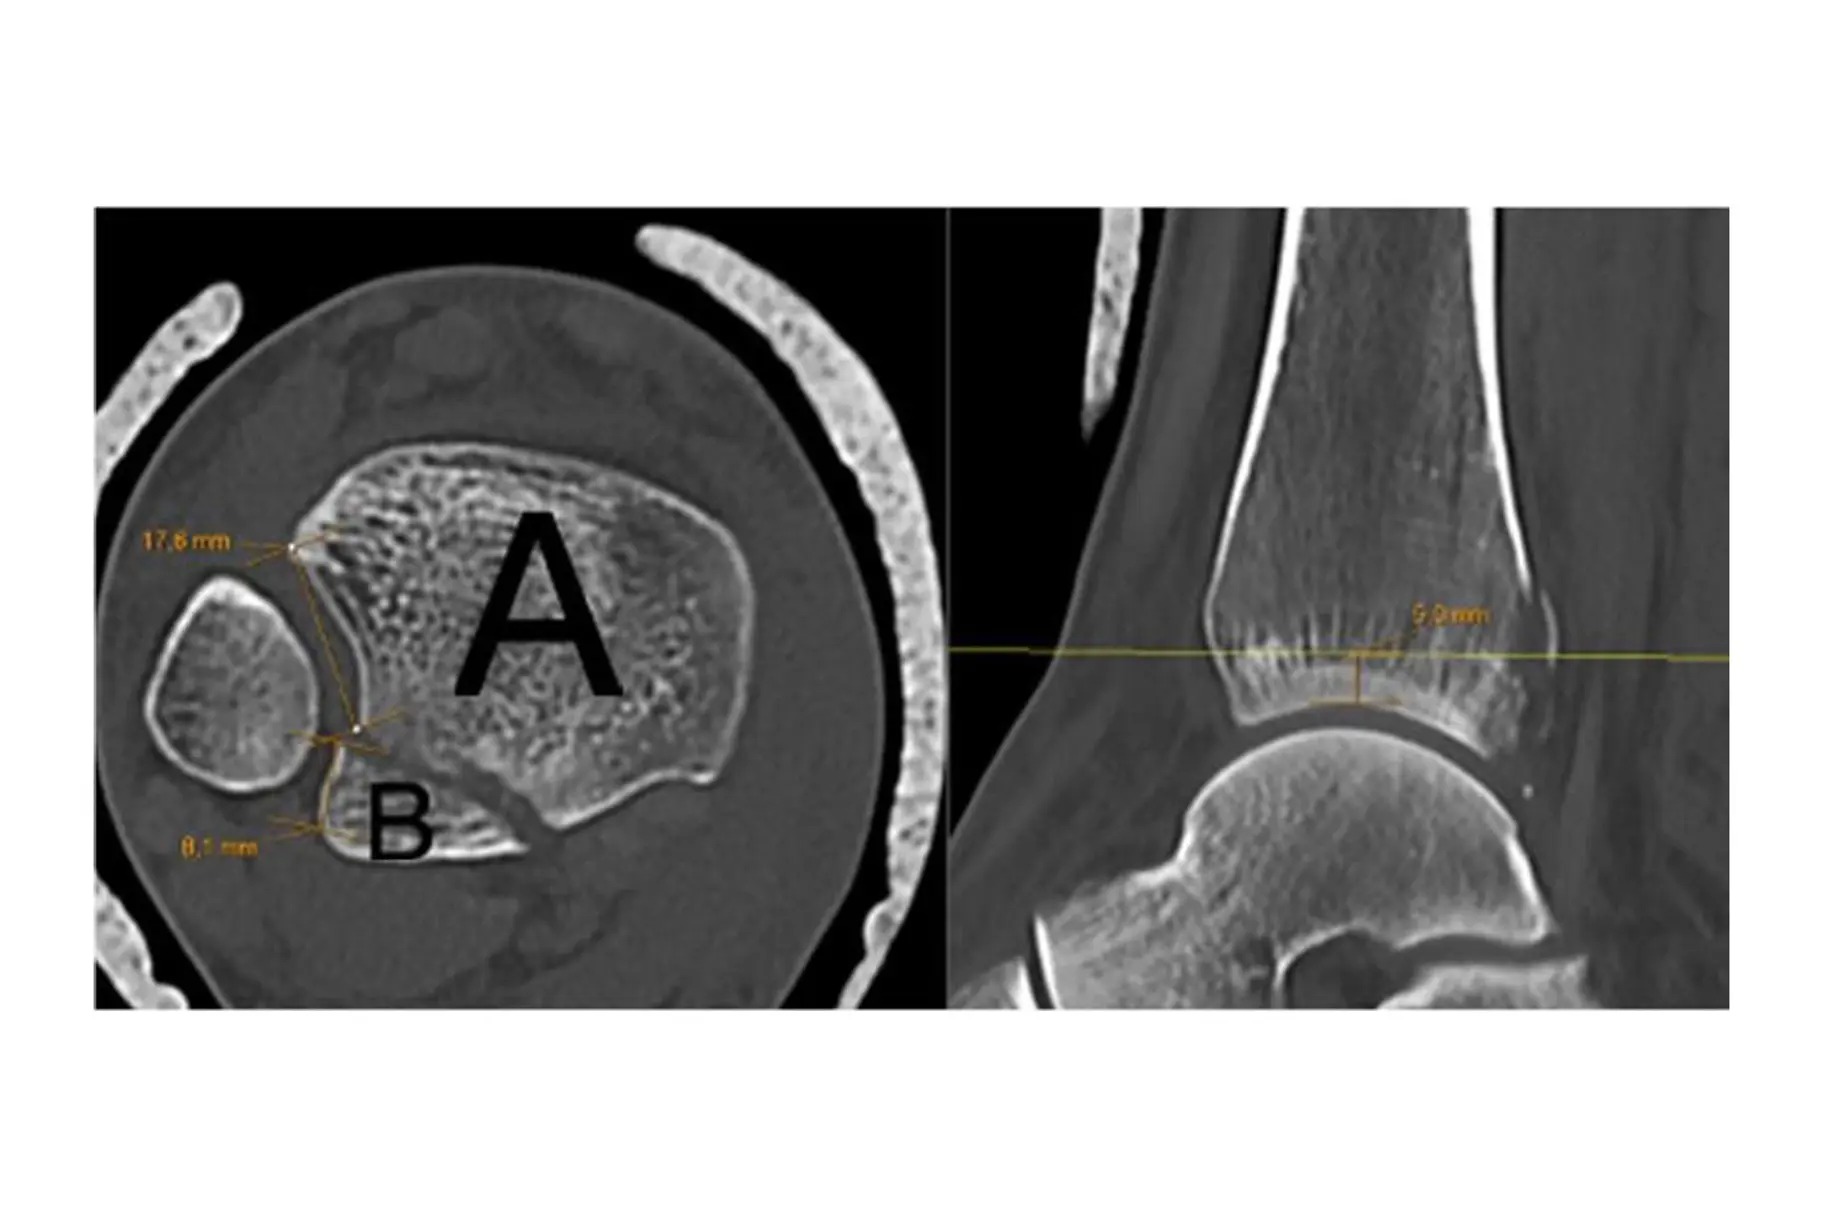

- Bakre malleol frakturer som involverer mindre enn 40 % av fibula notch kan inkluderes (Målinger utføres 5 millimeter (mm) over tibia plafonden. Se figur 2 for illustrasjon av målinger).

Figur 2 – Måling av notchinvolvering av posterolateralt fragment 5 mm over tibia plafonden.